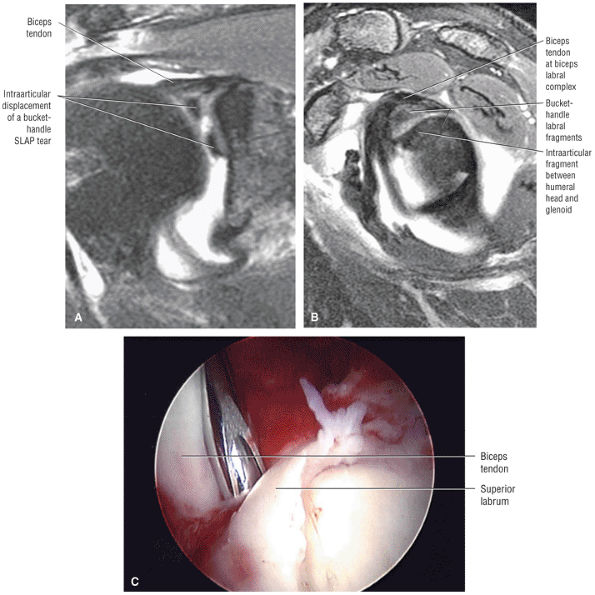

FIGURE 8.102 ● (A) The anterior undersurface of the acromion and the coracoacromial ligament form the coracoacromial arch. The subacromial subdeltoid bursa facilitates the passage of the rotator cuff and proximal humerus under the coracoacromial arch. (B) A superior axial image shows the anterior-to-posterior extent of the coracoacromial (CA) ligament perpendicular to the supraspinatus tendon. The fluid in the subacromial-subdeltoid bursa represents fluid between two serosal surfaces in contact with each other. One serosal surface is contributed by the undersurface of the coracoacromial arch and deltoid, and the other serosal surface is on the bursal side of the cuff.

|

![]() |

FIGURE 8.103 ● Pseudospur. The normal broad attachment of the coracoacromial ligament to the inferior surface of the acromion is shown on (A) T1-weighted coronal oblique and (B) sagittal oblique images. The low-signal-intensity acromial cortex (black arrows) and adjacent coracoacromial ligament and lateral slip of the deltoid attachment (white arrows) give the false impression of a small subacromial spur in the coronal plane. This pseudospur should not be misinterpreted as impingement; otherwise, unnecessary acromioplasties may be performed on patients with a normal coracoacromial ligament attachment and no associated acromial spurs.